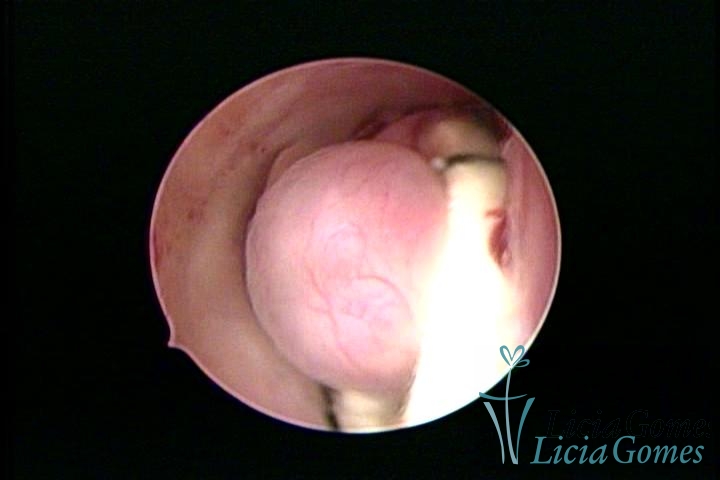

Dispositivo Mirena® e um mioma submucoso